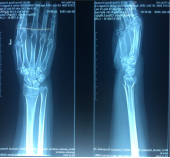

11月份门诊诊疗病例80余人次,病种大多为颈椎病、腰椎间盘突出症、腰椎管狭窄症、梨状肌紧张综合征、胸腰椎小关节紊乱症、小儿髋关节滑膜崁顿、膝关节骨性关节炎、膝关节滑膜炎、肩关节周围炎、股骨头坏死、距骨坏死及桡骨远端骨折、锁骨骨折、尺骨鹰嘴骨折、尺骨骨折、股骨颈骨折、股骨大粗隆撕脱骨折、踝关节骨折、掌骨骨折、指骨骨折、跖骨骨折、趾骨骨折、肩关节脱位等。

手法整复桡骨远端骨折、踝关节骨折、尺骨骨折、掌骨骨折、指骨骨折、跖骨骨折及肩关节脱位、桡骨小头半脱位等各类骨折脱位十余例,行小夹板固定及石膏托外固定十余例。